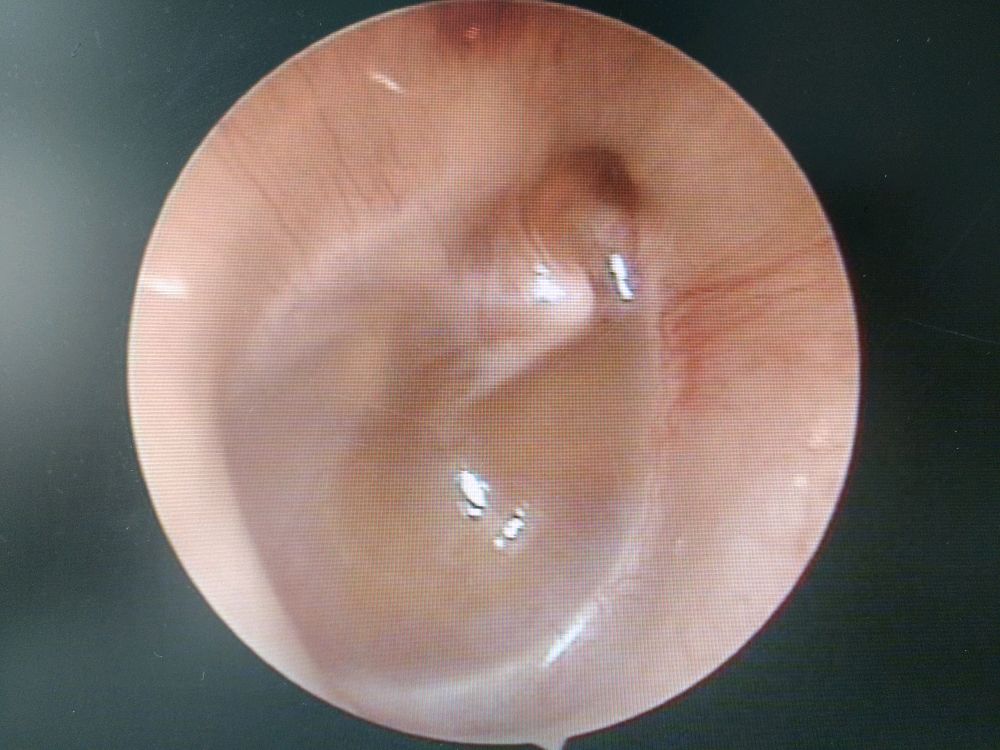

中耳炎耳镜检查危害图片_纵览新闻

慢性化脓性中耳炎

中耳疾病之慢性化脓性中耳炎